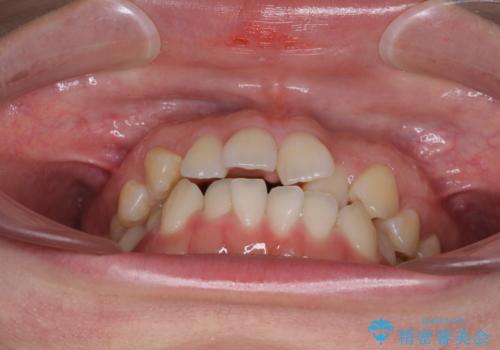

前歯のデコボコを治したい ワイヤー矯正

- 前歯のデコボコが気になるとのことで来院された患者様です。

1年半程度の期間を見込んでいましたが、上下の真ん中の位置をできる限り合わせるための調整に少し時間がかかってしまいました。